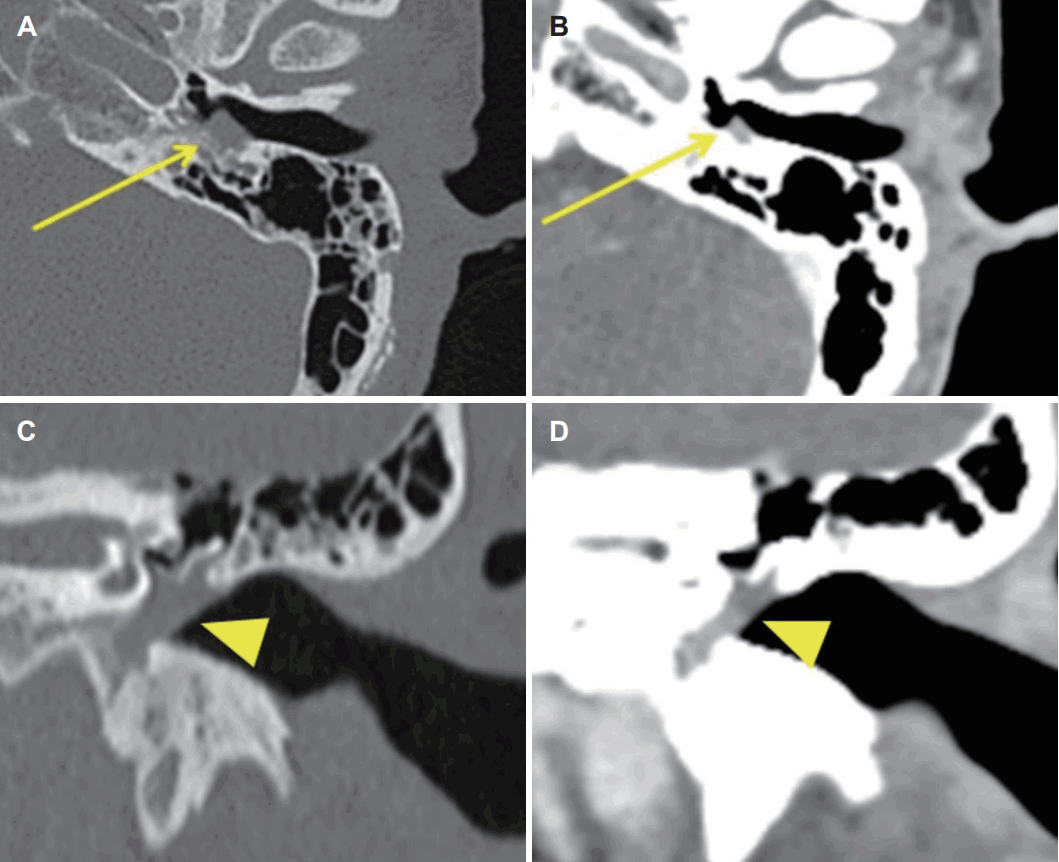

문진상 좌측 청력저하를 호소하였고 그 외 이루, 이통 및 현훈 등의 증상은 호소하지 않았다. 신체 검진상 안면 비대칭은 없었고, 고막 내시경 검사상 양측 고막에서 천공은 보이지 않았고, 좌측 고막에 중이강 내 저류액 소견 및 고막 상방의 팽윤 소견이 관찰되었다(Fig. 1). 순음청력검사에서 우측 기도청력 20 dB HL, 골도청력 20 dB HL, 좌측 기도청력 30 dB HL, 골도청력 25 dB HL으로 확인되었다(이상 6분법) (Fig. 2). 조영증강 측두골 전산화단층촬영 영상에서 좌측 중이강 내 연조직 강도의 음영이 관찰되었으며 하고실을 채우고 있는 음영의 경우 조영증강이 동반되는 반면에, 상고실에서 관찰된 음영의 경우 조영증강이 되지 않았다. 이관 및 이관 입구부위는 폐쇄된 소견은 관찰되지 않았고 비인두강 내 특이소견도 관찰되지 않았다(Fig. 3). 위 소견들을 바탕으로 좌측 진주종 및 삼출성 중이염 의심하에 좌측 내시경 및 현미경을 이용한 시험적 개방술을 통한 진주종 제거를 계획하였고 필요시 공동폐쇄 유양동 절제술 및 고실 성형술을 고려하여 수술을 준비하였다.

Preoperative CT of temporal bone. A: Non-contrast horizontal plane of left middle ear. B: Contrast horizontal plane of left middle ear. C: Non-contrast coronal plane of left middle ear. D: Contrast coronal plane of left middle ear. Horizontal CT shows soft tissue density lesion in left middle ear cavity (arrows) and coronal CT shows enhanced mass of hypotympanum (arrowheads).